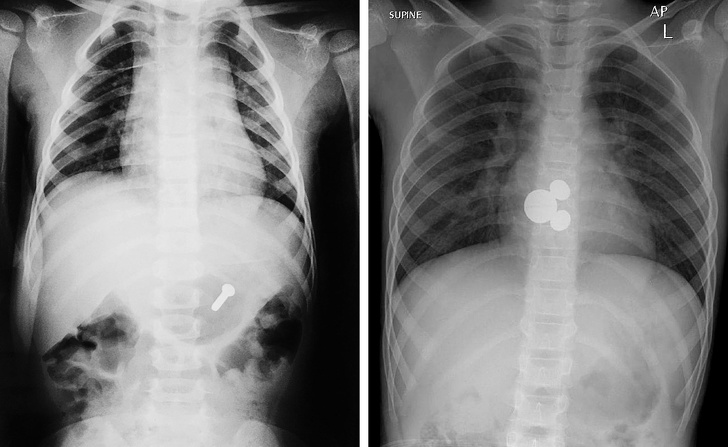

13. Ось чому не можна дозволяти дітям грати з дрібними предметами